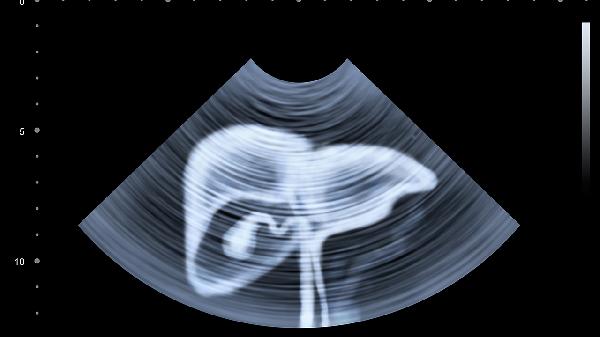

52岁女子体检报告上的"肝癌"二字,让全家人都慌了神。医生详细询问生活习惯后,目光锁定在厨房里那个用了3年都没换的木质砧板上——那些深深浅浅的刀痕里,藏着比砧板更"老"的黄曲霉菌。这种一级致癌物,正在悄悄攻击全家人的肝脏。